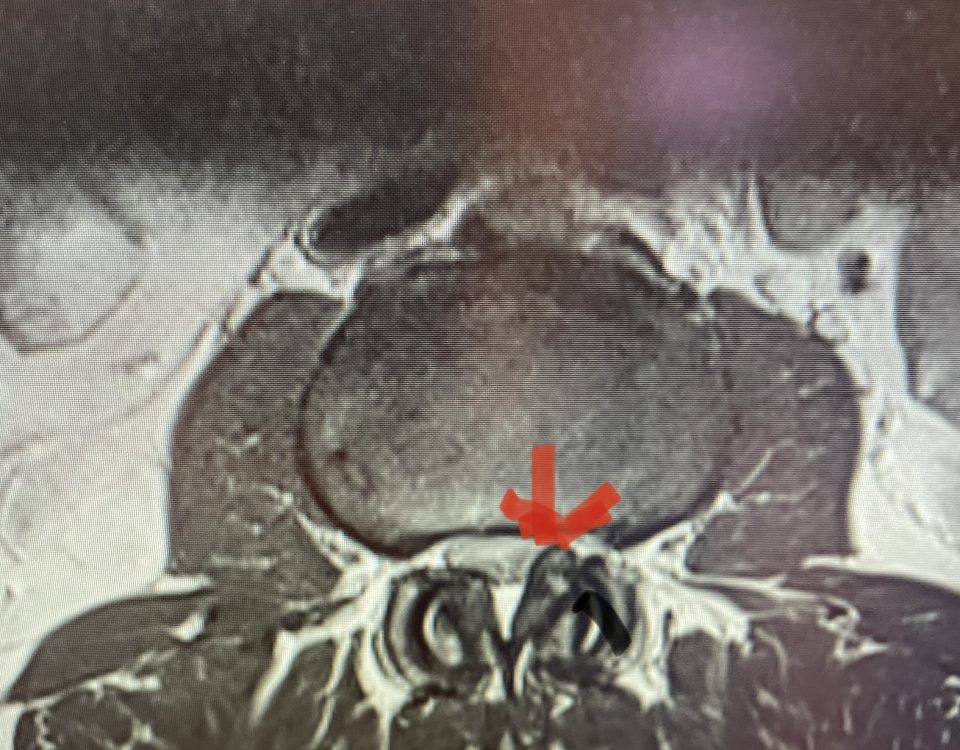

The actual structural cause of lumbar thecal sac compression can vary in degenerative spondylolisthesis and stenosis. The culprits are commonly thickened ligamentum flavum or severe facet […]

Nervous tissue is soft. The thecal sac is surrounded by a rigid bony ring which forms the spinal canal. Any mass that fills the very small […]